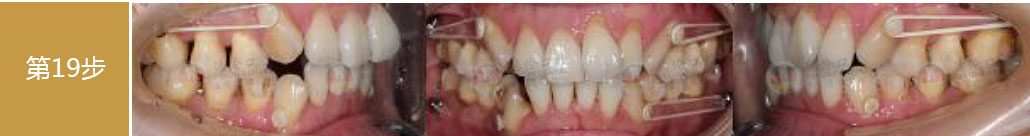

矯治前后對(duì)比

蛻變周期:上頜16個(gè)月,矯治效率提升30%,下頜12個(gè)月,矯治效率提升20%

矯

治

后

口

內(nèi)

照